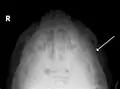

قوس گونه (انگلیسی: Zygomatic arch) که بخشی از استخوان گونه است که موجب برجستگی گونهها میشود. قوس گونه یک ستیغ استخوانی است که در فاصله زبانه گوش و لاله گوش و نقطه یوغی قرار دارد و به راحتی قابل لمس است. برای لمس قوس بهتر است انگشتان از پایین به بالا حرکت کند. نقطه یوغی (Jugal point) که نقطه گونهای هم نامیده میشود نقطهای است که در زاویه بین قوس گونهای و زایده پیشانی استخوان گونه قرار دارد و قابل لمس است.

استخوان گیجگاهی از سه بخش تشکیل شده است. اول خاره که هرمی شکل است و در قاعده کاسه سر واقع شده است. قسمت دوم صدف نام دارد که ناحیه گیجگاهی را تشکیل میدهد. در زیر صدف زائدهای از زیر این استخوان خارج میشود که زائده گونهای نام دارد و با استخوان گونه مفصل شده و قوس گونهای را به وجود میآورد. این قوس در زیر پوست قرار داشته و بسیار ظریف است به طوری که در اثر ضربه مستقیم فوراً میشکند.